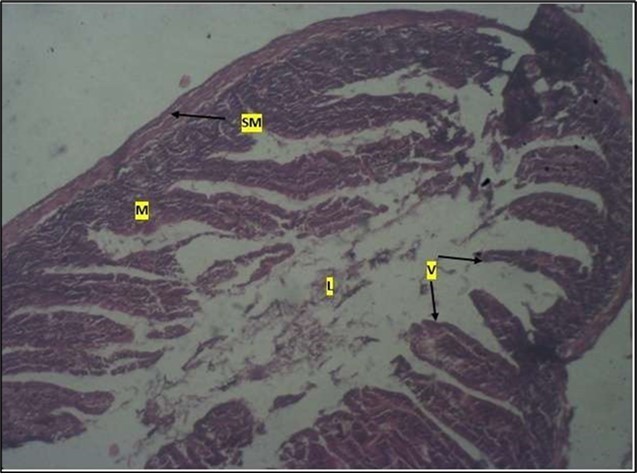

Micrographs of The Small Intestine

Histological examination of the small intestine result in control animals revealed a normal architecture with the red pulp and white pulp with no pathological observation Figure 2. Administration of Abelmoschus esculentus at low dose shows an increased cellularity with numerous cells in the Mucosa and the villi projecting towards the lumen. Focal metaplasia of mucosal cells alongside villous disruption was also observed (Figure 3). The high dose group showed normal cellular architecture with no villous disruption (Figure 4).

Figure 3.Low dose showing numerous epithelial cells in the mucosa (m) with villi projecting towards the lumen (l). The is focal metaplasia of the mucosal cells with villous disruption. smooth muscle layer appears normal. H & E. X40